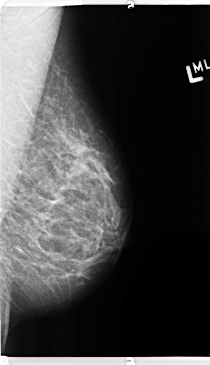

B_3145_1.RIGHT_CC

LEFT_CC LINES 4768 PIXELS_PER_LINE 2512 BITS_PER_PIXEL 12 RESOLUTION 50 NON_OVERLAY